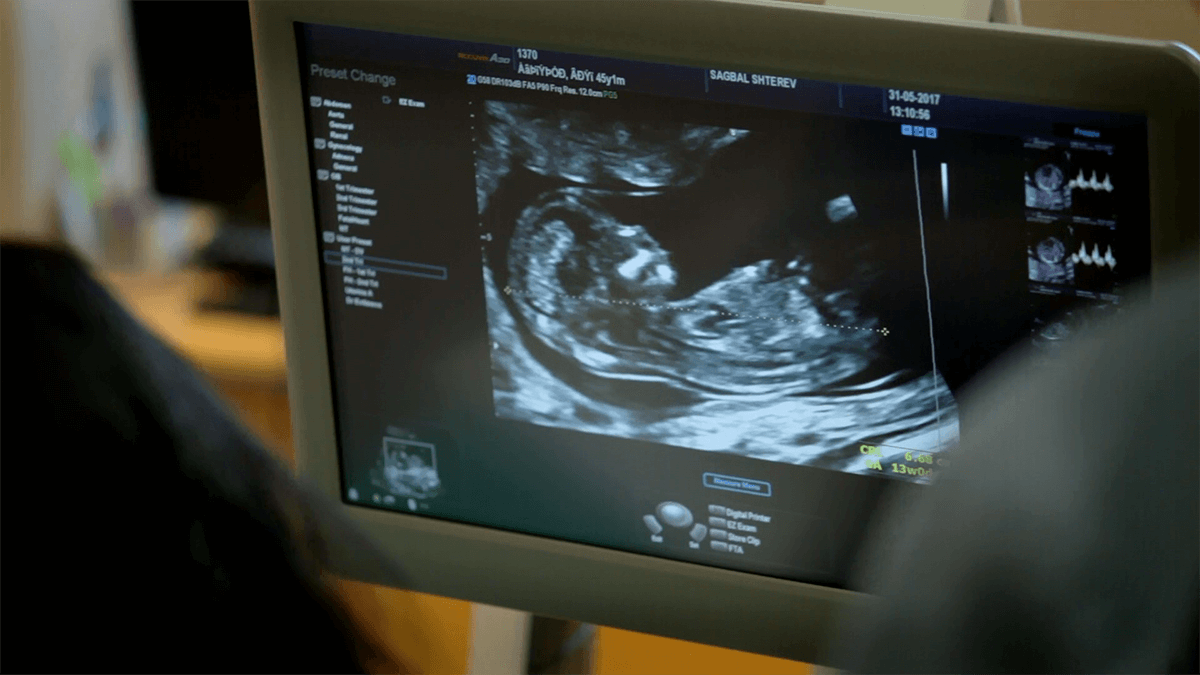

A ecografia morfológica do terceiro trimestre é um exame crucial para avaliar o estado de saúde do bebé e da mãe nas últimas semanas de gestação. Realizada geralmente entre as 28 e 32 semanas, este exame tem como objectivo garantir que o bebé está a desenvolver-se bem e que está tudo preparado para um parto seguro. Além disso, oferece uma visão detalhada de como o bebé está posicionado e de qualquer eventualidade que possa exigir atenção médica antes do nascimento.

A ecografia morfológica do terceiro trimestre é uma ultrassonografia realizada para verificar o desenvolvimento do bebé nas últimas etapas da gravidez. Esta ecografia foca-se, principalmente, no crescimento fetal, na posição do bebé, na quantidade de líquido amniótico e no funcionamento da placenta, assegurando que todas as condições estão adequadas para o nascimento.

O período ideal para a realização da ecografia morfológica do terceiro trimestre é entre as 28 e 32 semanas de gestação. Nesse estágio, o bebé já está suficientemente desenvolvido, o que permite uma análise mais detalhada de seu crescimento e das condições que influenciam o parto.

A ecografia do terceiro trimestre é realizada de forma semelhante às anteriores, com a gestante deitada enquanto o médico aplica um gel no abdómen para facilitar a transmissão das ondas de ultrassom. A duração do exame varia entre 20 a 30 minutos, dependendo da necessidade de observação de detalhes ou da posição do bebé.